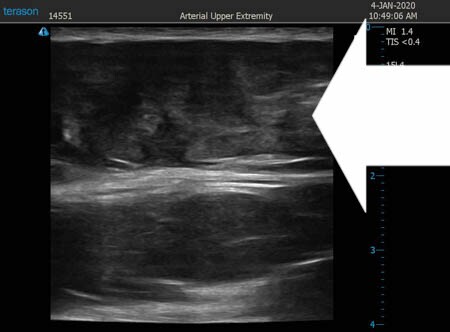

いつものように3Dタッチビュー(超音波)で

皮下脂肪層を評価してみましょう。

上腹部